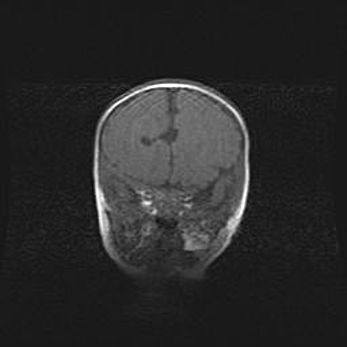

Множественные кисты обоих полушарий головного мозга, наибольшая из них в правой затылочной области. Ассиметричная атрофическая гидроцефалия.

Возраст: 7 месяцев

Вес: 5660 г

Пол: мужской

Окружность головы: 41,5 см

Срок гестации: 28-29 недель

Кисты головного мозга развиваются в результате многоочаговых некрозов вещества мозга и возникают вследствие перенесенной перинатальной инфекции, менингитов, энцефалитов, асфиксии, родовой травмы, расстройств мозгового кровообращения различного генеза. Образованию кист в веществе головного мозга плодов и новорожденных способствуют такие факторы, как высокое содержание в нем воды, недостаточная (или отсутствие) миелинизация и слабая астроглиальная реакция на повреждение.

Кисты могут сочетаться с гидроцефалией и другими поражениями головного мозга.